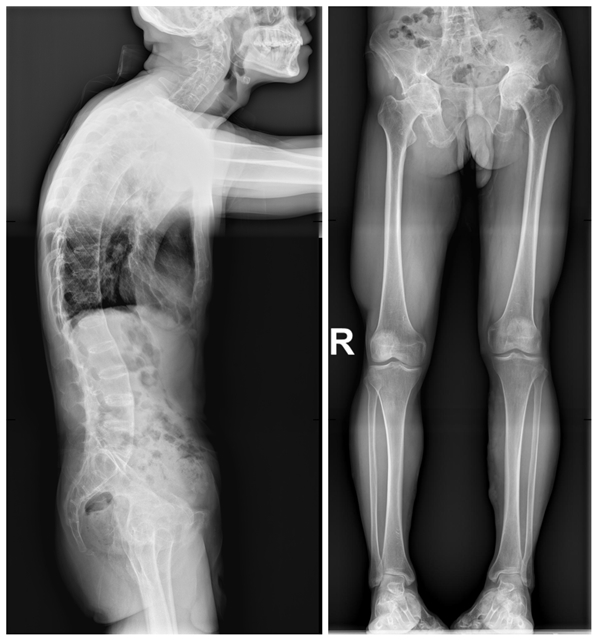

术前体态徐驰副主任根据患者病情,结合查体、影像学检查,认为只有实施手术治疗才能改善患者的行走功能,提高患者的生活质量。徐驰团队制定了详细的手术方案,患者目前最核心的问题是双侧髋关节疼痛、行走严重障碍,双侧髋关节屈伸功能明显受限,可行双侧全髋关节置换术,以人工关节替代损毁关节,重建结构,恢复功能。但由于患者股骨头和髋臼几乎已经骨性融合,手术难度较大、时间较长,为了降低手术风险,决定分两次对其进行全髋关节置换术。

脊柱出现骨性融合、 双髋关节间隙基本消失经过充分的术前准备,2021年7月9日,在徐驰主任的主刀下,为温先生实施了后外侧入路左侧人工全髋关节置换术。手术很顺利,取得了满意的效果。团队根据其康复的实际情况,于2022年8月24日对其右侧的髋关节也进行人工全髋关节置换术。

左髋置换术后、双髋置换术后术后第二天,温先生在没有助行器、没有拐杖辅助的情况下,自由下地行走,步态较之前明显改善,生活质量得到了明显提高,对患者以及家庭都是一个新的开始!